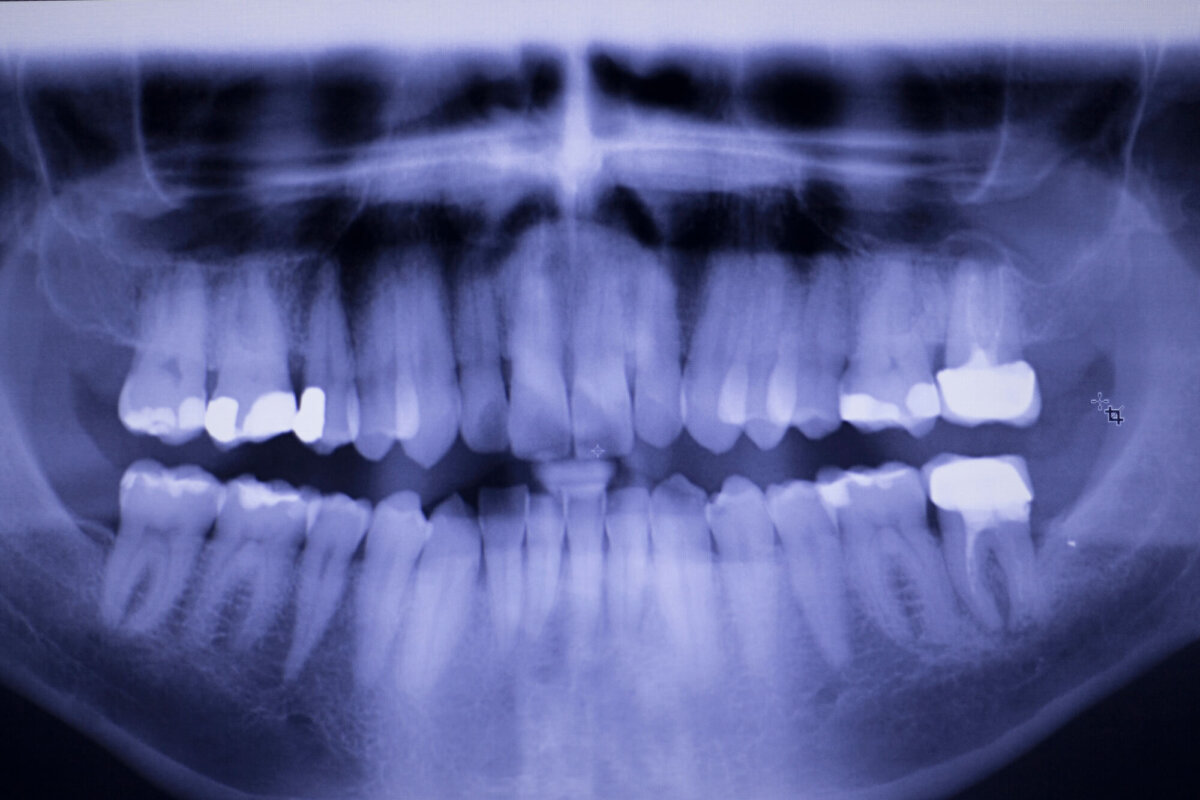

Even if you don’t notice any of these symptoms, regular checkups are essential. Dentists can spot early decay with X-rays or thorough exams, catching problems before you feel them.